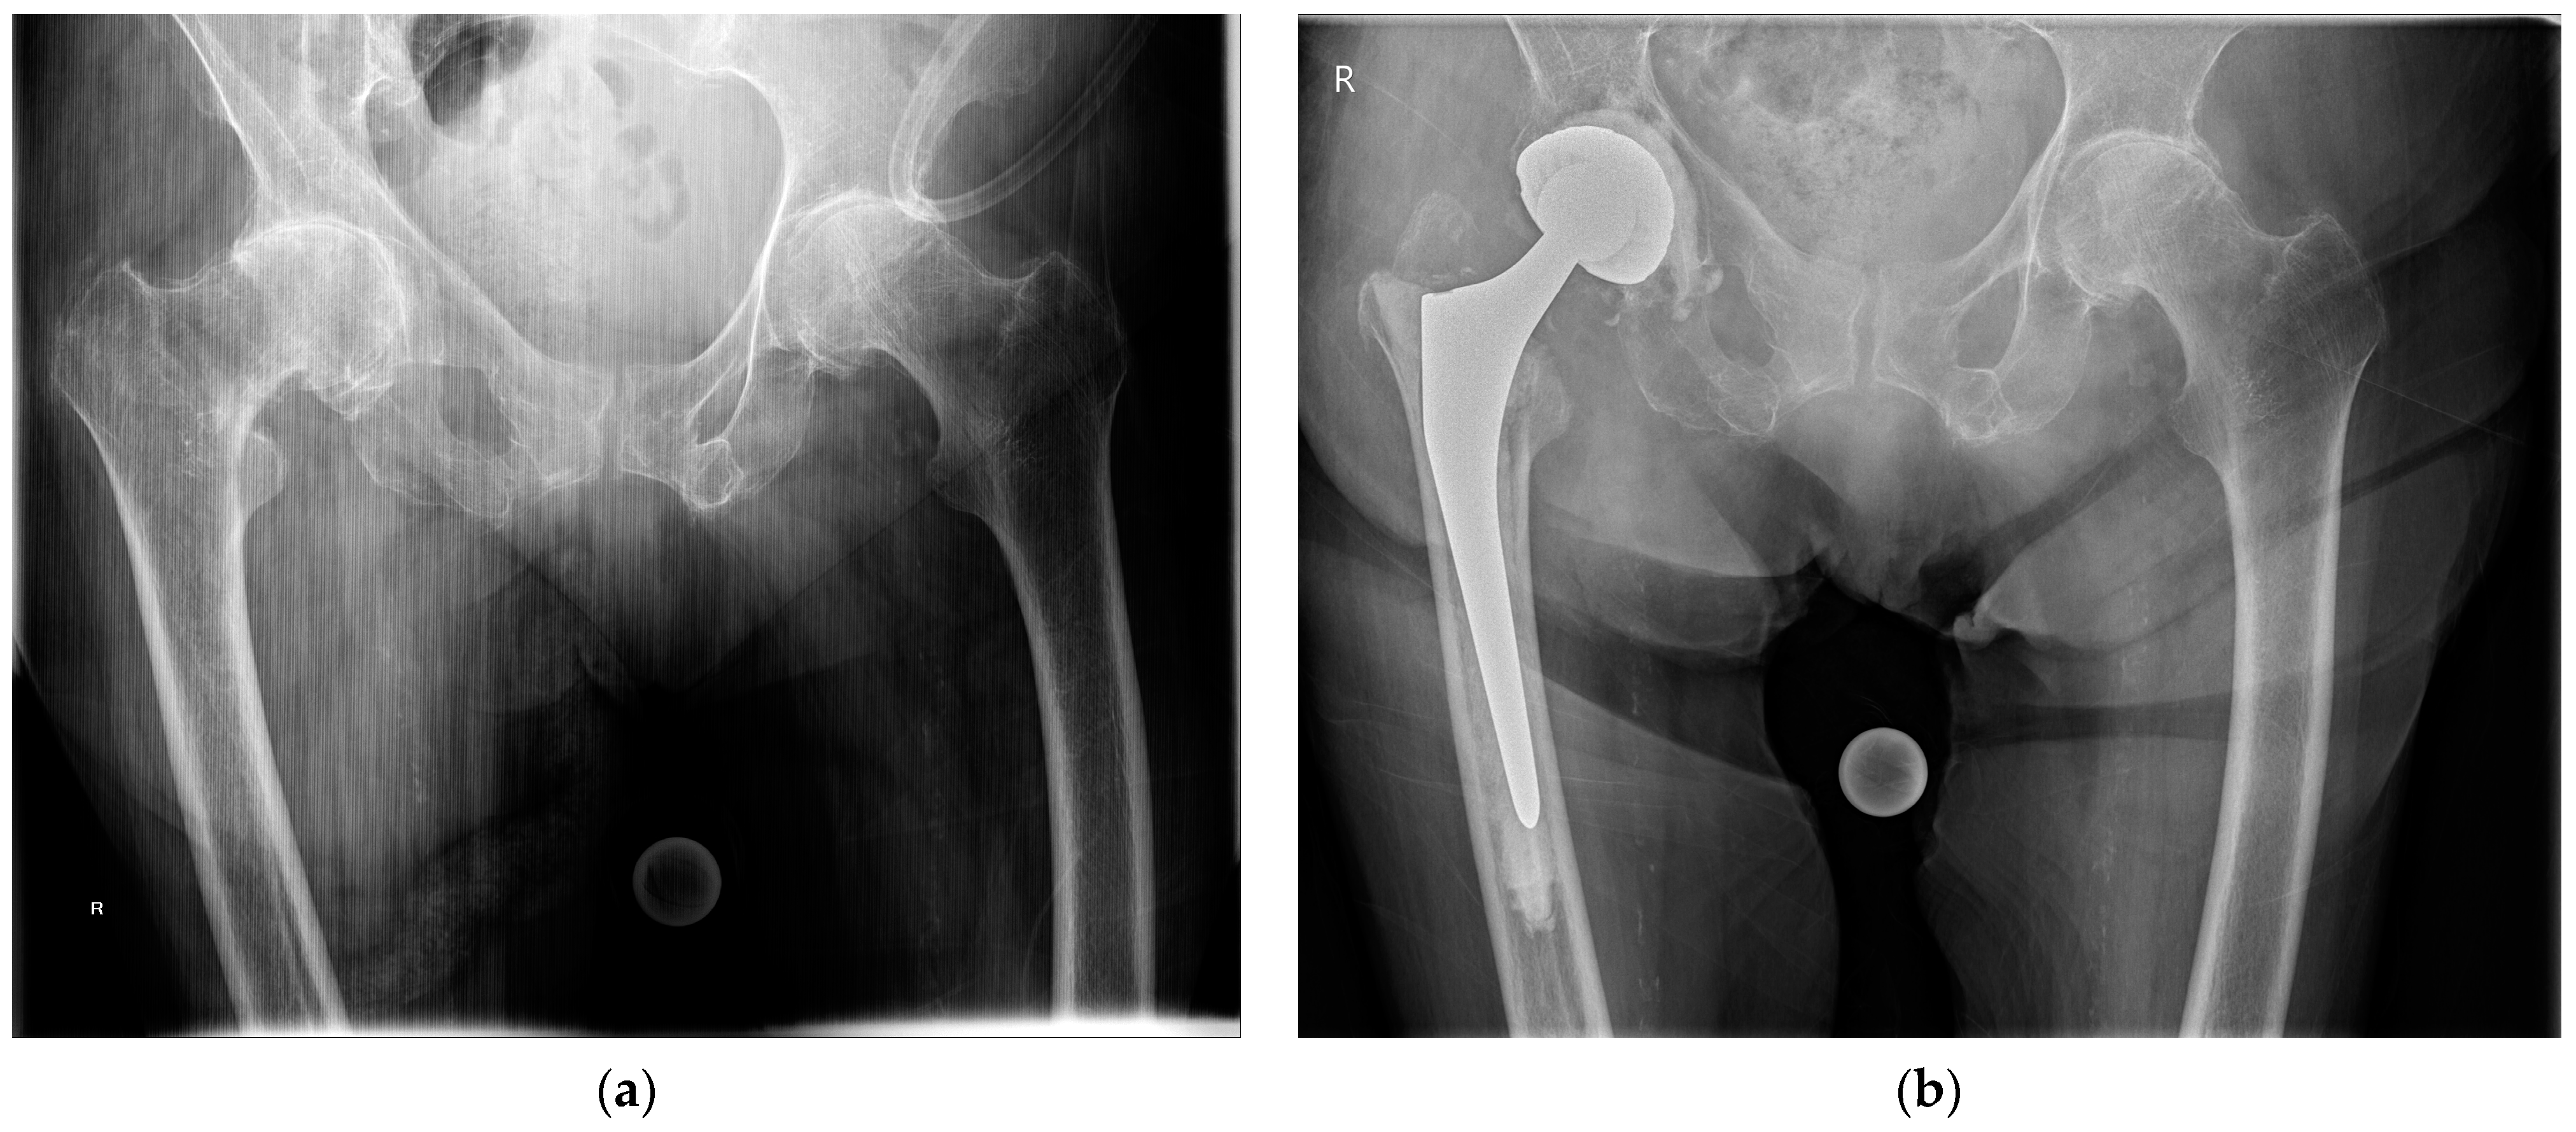

Figure 1.

(a) Preoperative anteroposterior pelvic radiograph of an intertrochanteric femur fracture with concomitant advanced osteoarthritis of the right hip; (b) anteroposterior pelvic radiograph at 1 year after total hip arthroplasty with a cemented femoral stem and a cemented double-mobility acetabular cup.